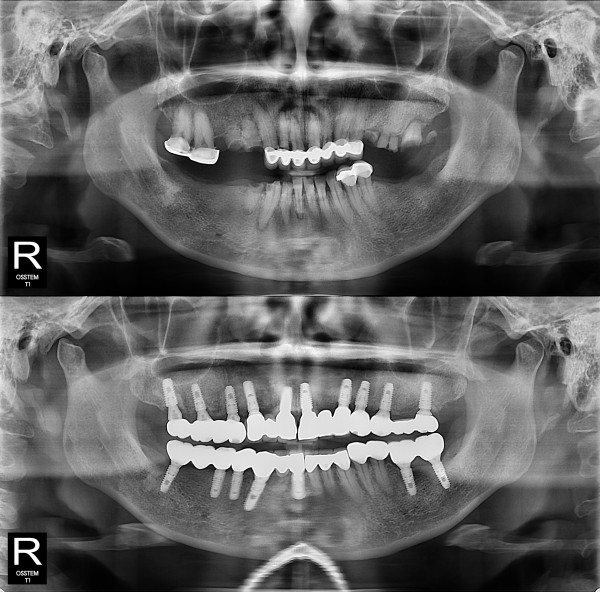

种植牙

全口种植牙